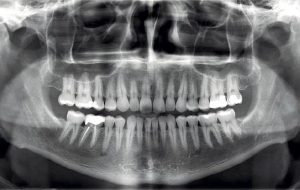

Hablar de la ortopantomografía es hablar de un tipo de técnica particular radiográfica panorámica en la que en una única imagen se pueden observar la parte maxilar, de la mandíbula y los dientes del paciente con el fin de brindar un diagnóstico preciso y ver las posibles patologías o alteraciones que puede sufrir.

En una ortopantomografía la mandíbula se ve en forma de U y los cóndilos se sitúan a unos 2,5 centímetros de los bordes de la película. Las raíces se pueden observar claramente en ambos lados.

- Caries dentales: en la ortopantomografía se podrá ver si existen caries dentales, aunque de una manera general, si se quiere ver específicamente se solicitara una periapical solo del área.

- Infecciones: cuando hay infecciones, en ocasiones estas lesiones llegan a expandirse más allá del diente y llegan a tocar otros dientes cercanos o hacer lesiones en el hueso.

- Dientes que aún no han erupcionado: en estos casos se ven los gérmenes dentales que están en formación y representan a esos dientes que aún no han salido en la boca.

- Erupción de los dientes en niños: cuando los niños aún tienen su dentadura temporal o mixta se puede ver una cronología de si los dientes han caído en el momento correcto o antes y así poder aplicar un tratamiento si hace falta.

- Lesiones óseas patológicas: se puede valorar la anatomía en el tabique nasal, presencia de asimetrías, senos maxilares, entre otros.

A la ortopantomografía se le llama también radiografía panorámica y se trata de un estudio radiológico en donde se pueden ver todos los dientes además de los tejidos y estructuras anatómicas.

Como es una radiografía bidimensional, permite ver los objetivos con mayor volumen y por ende las imágenes se pueden ver superpuestas. Aunque es una radiografía muy útil, en ocasiones la superposición podría no ser beneficiosa ya que no permite ver algunas patologías en concreto.

Si en la imagen se ven zonas oscuras, eso quiere decir que hay ausencia de tejido duro y por lo tanto de caries.

Otra de las informaciones que nos brinda la ortopantomografía es la extensión de la caries y si hay contacto o no con el nervio del diente, algo fundamental ya que podría causar otro tipo de inconvenientes.